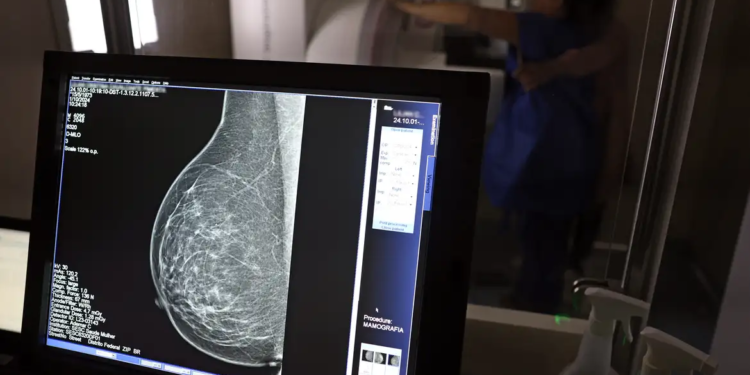

No mês de conscientização sobre o câncer de mama, um relatório destaca a importância de acesso igualitário ao rastreamento e tratamento da doença. Segundo o Atlas da Radiologia no Brasil, do Colégio Brasileiro de Radiologia e Diagnóstico por Imagem (CBR), o acesso aos mamógrafos ainda é um desafio.

O país tem 6.826 equipamentos registrados, sendo 96% em funcionamento. Metade deles está disponível no Sistema Único de Saúde (SUS), responsável por atender 75% da população. Isso equivale a 2,13 mamógrafos por 100 mil habitantes dependentes do SUS.

Na saúde suplementar, que cobre 25% da população, o cenário é mais favorável: 6,54 aparelhos por 100 mil beneficiárias, quase o triplo da rede pública. O Acre exemplifica essa disparidade — são 35,38 mamógrafos por 100 mil habitantes na rede privada, contra 0,84 no SUS.

Há disparidades regionais. Roraima tem a menor proporção (1,53 por 100 mil), seguida do Ceará (2,23) e Pará (2,25). A Paraíba lidera o ranking (4,32), à frente do Distrito Federal (4,26) e do Rio de Janeiro (3,93).

O Brasil tem uma cobertura muito baixa de mamografias: 24%. O ideal recomendado pela Organização Mundial da Saúde é de 70%. Mesmo em lugares como o estado de São Paulo, que tem a maior concentração de mamógrafos do país, a taxa gira em torno de 26%.

Em setembro, o Ministério da Saúde ampliou as diretrizes de rastreamento, recomendando que mulheres entre 40 e 49 anos realizem mamografias, mesmo sem sintomas. De acordo com o Instituto Nacional do Câncer (Imca), mais de 73 mil mulheres recebem o diagnóstico de câncer de mama anualmente no Brasil.

“O que é efetivo na redução da mortalidade é você descobrir o tumor antes de ter sintoma clínico. Quanto menor o tumor, melhor para a gente descobrir o tratamento e maior a chance de cura. E a gente só consegue fazer isso com exames de imagem”, diz Ivie.

Ela explica que no caso de diagnóstico de um câncer de mama com menos de 1 cm, a chance de cura é de 95% em cinco anos, independentemente se ele é do tipo mais agressivo. “E esses tumores só vão ser detectados na mamografia. Essas pessoas que têm que ir fazer mamografia são mulheres saudáveis. Não são mulheres doentes”, acrescenta.